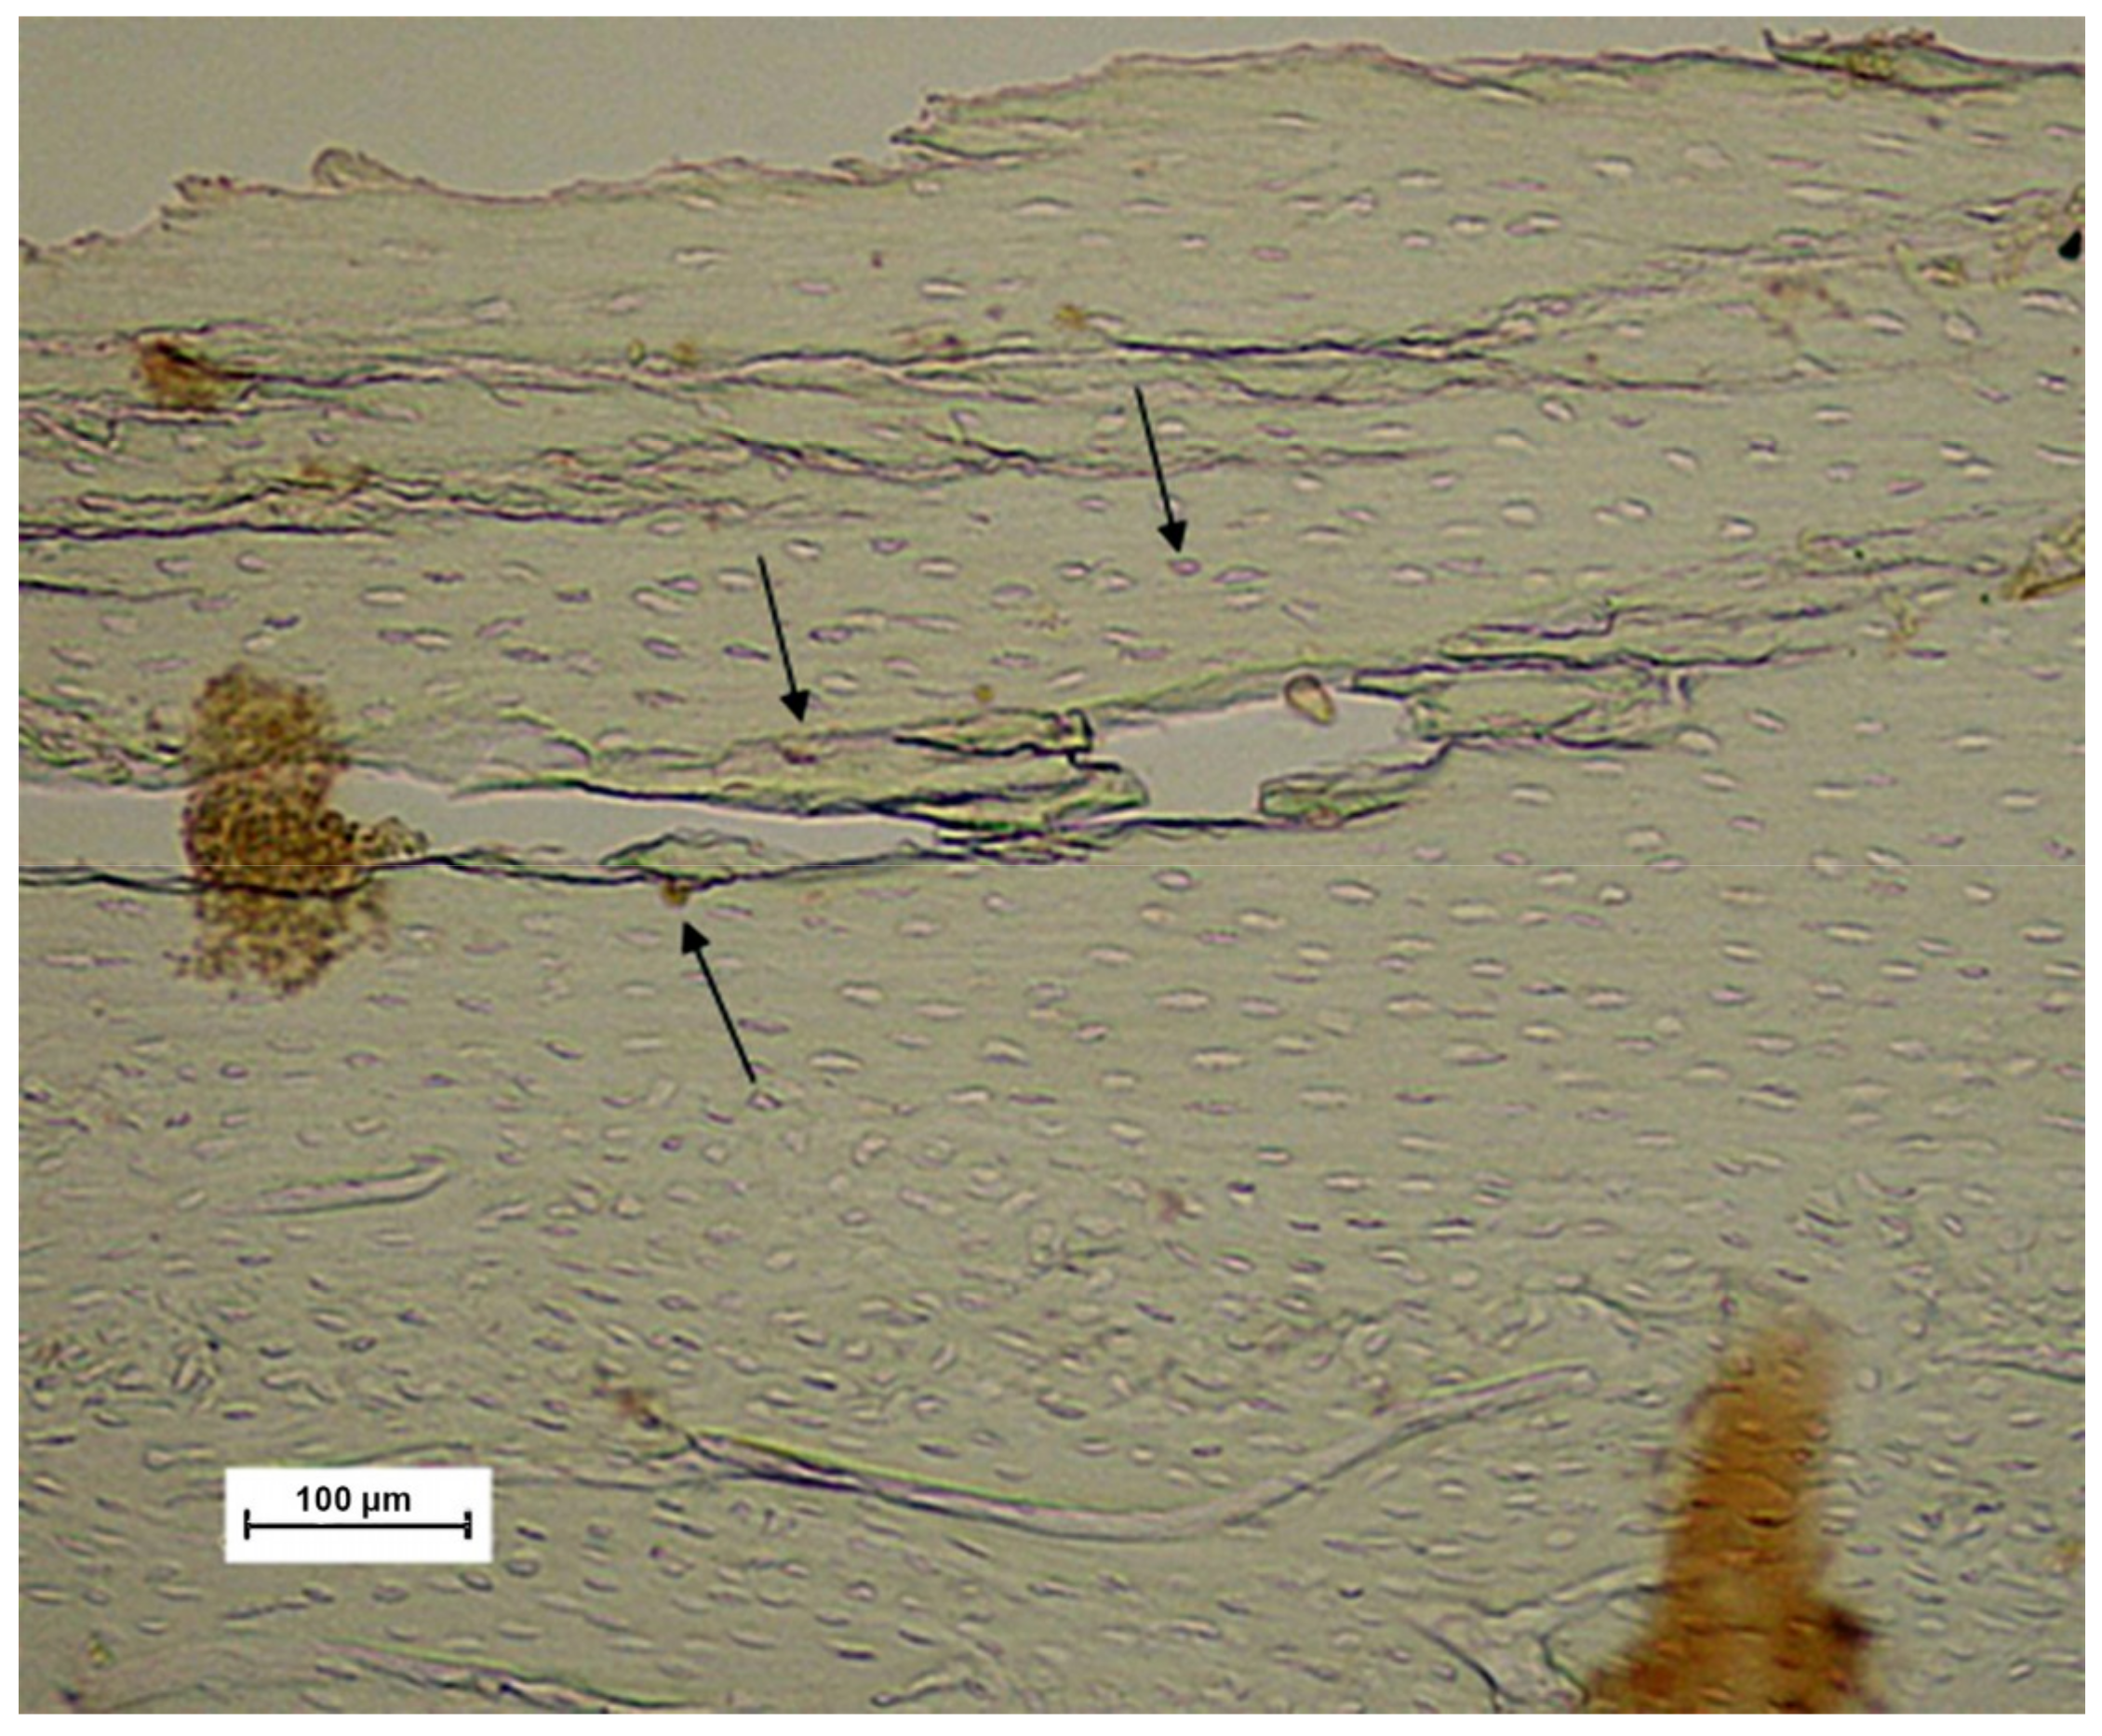

2.5. Immunohistochemical Process

- Salles, M.B.; Konig, B., Jr.; Allegrini, S., Jr.; Yoshimoto, M.; Martins, M.T.; Coelho, P.G. Identification of the nuclear factor kappa-beta (NF-κB) in cortical of mice Wistar using Technovit 7200 VCR(R). Med. Oral Patol. Oral Cir. Bucal 2011, 16, e124–e131. [Google Scholar] [CrossRef]

- Donath, K.; Breuner, G. A method for the study of undecalcified bones and teeth with attached soft tissues. The Sage-Schliff (sawing and grinding) technique. J. Oral. Pathol. 1982, 11, 318–326. [Google Scholar] [CrossRef]